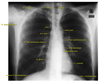

What structures outline the mediastinum on CXR?

A